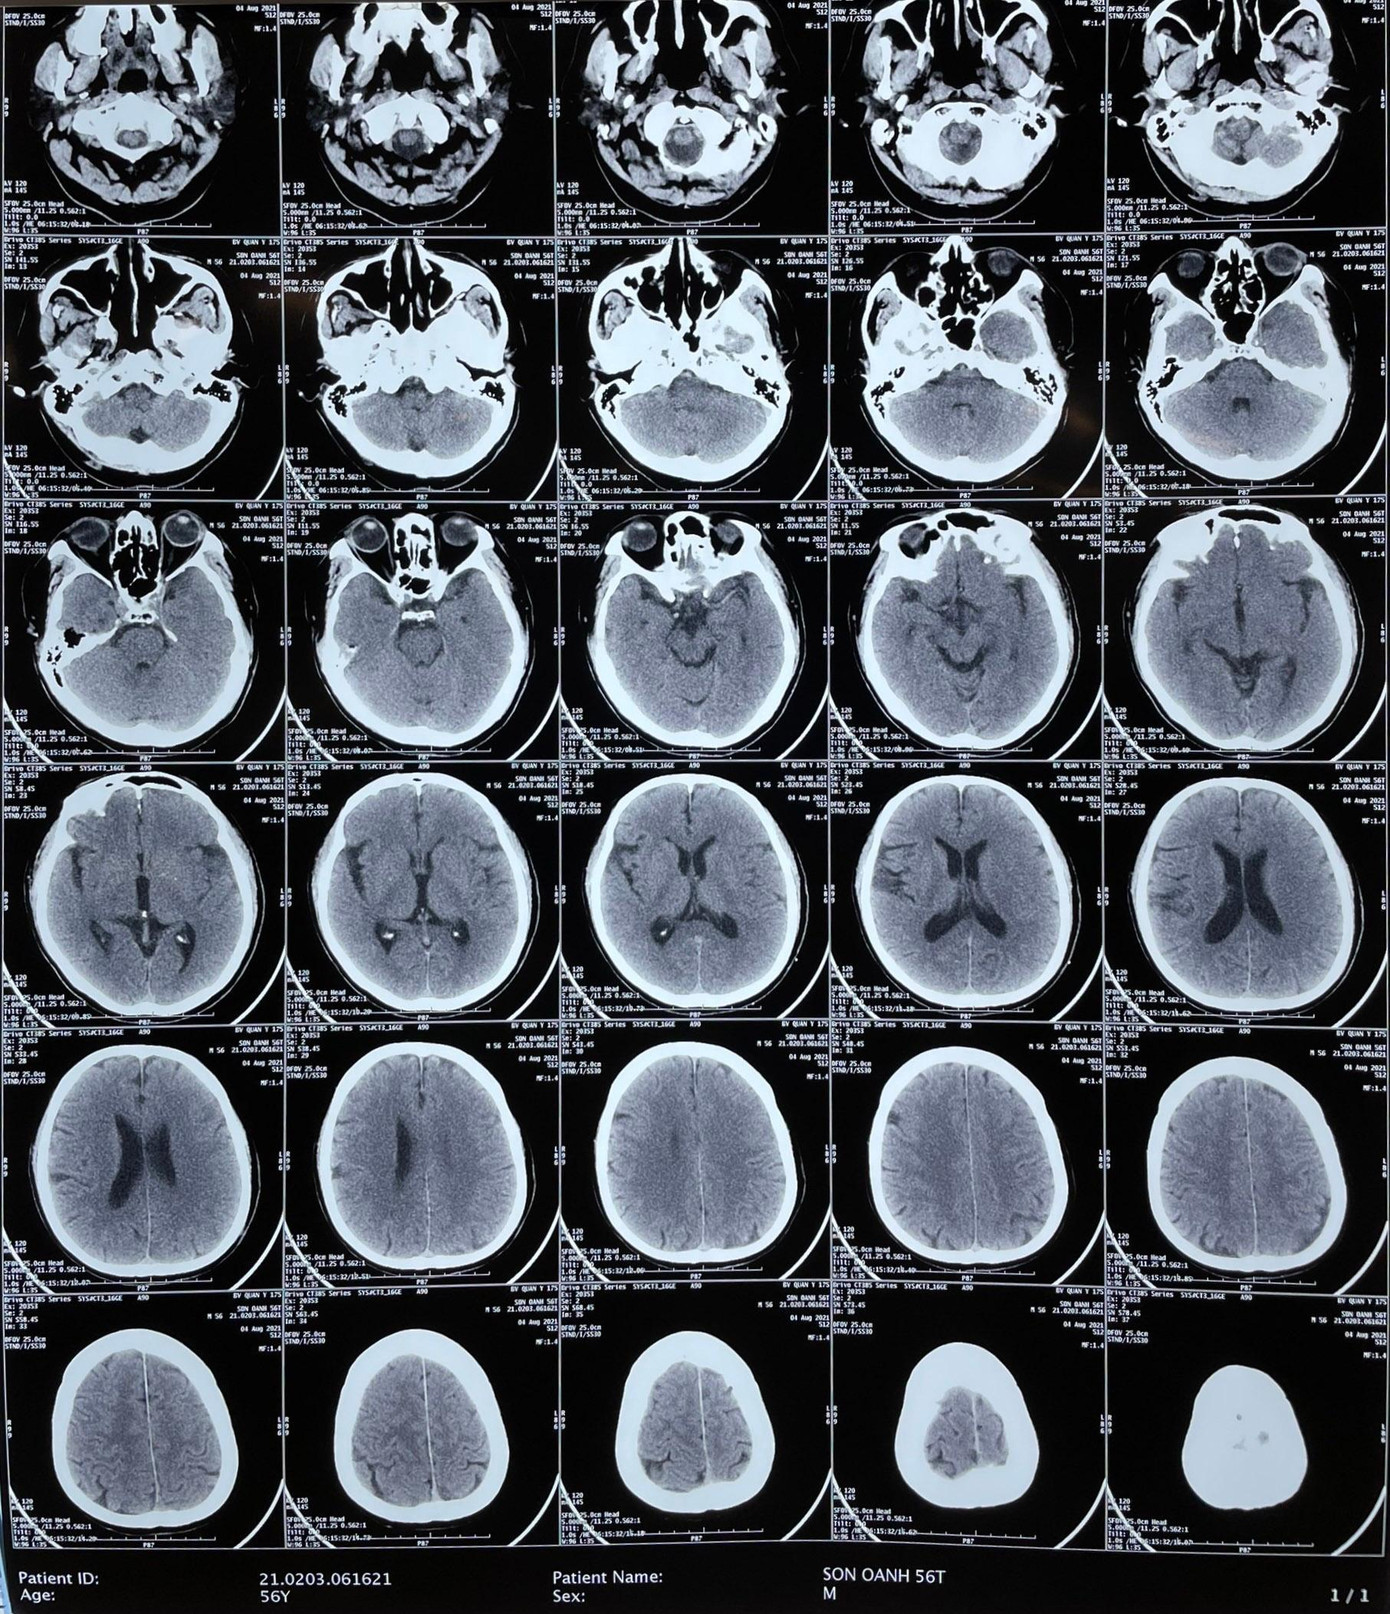

Qua chụp CT, bác sĩ phát hiện bệnh nhân bị tắc hoàn toàn động mạch não giữa phía bên trái đoạn gốc. Thiếu tá - bác sỹ Tạ Vương Khoa cùng ekip tiến hành điều trị bắt cầu tiêu sợi huyết và can thiệp mạch để lấy huyết khối bằng dụng cụ cơ học.

Trong quá trình chụp mạch não ghi nhận tổn thương huyết khối tắc hoàn toàn đoạn gốc trên nền hẹp xơ vữa nặng. Ekip nhanh chóng lấy huyết khối bằng Stent và nong bóng đoạn gốc động mạch não giữa bên trái. Sau khi can thiệp đã tái thông mạch, kết thúc can thiệp bệnh nhân tỉnh liệt 1/2 người bên phải đã được cải thiện, sau can thiệp chưa ghi nhận các tổn thương mới.

| Hình ảnh chụp CT não bệnh nhân. |